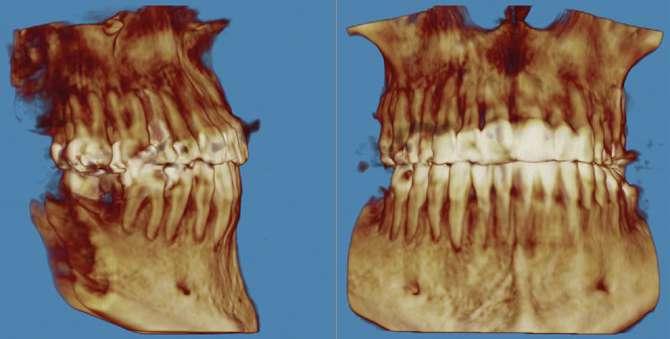

3. Análisis radiográfico y tomográfico (Ilustración 4):

 Constricción maxilar con deficiencia transversal

> 5 mm.

 Clase III esquelética.

 Patrón esquelético hiperdivergente con el plano oclusal mandibular compensado con rotación anti-horaria.

 Sutura palatina media parcialmente osificada (8) (9).

 Posición de terceros molares no favorable, por lo que se recomendó extracción.

Ilustración 4. Registros radiográficos iniciales de estudio.